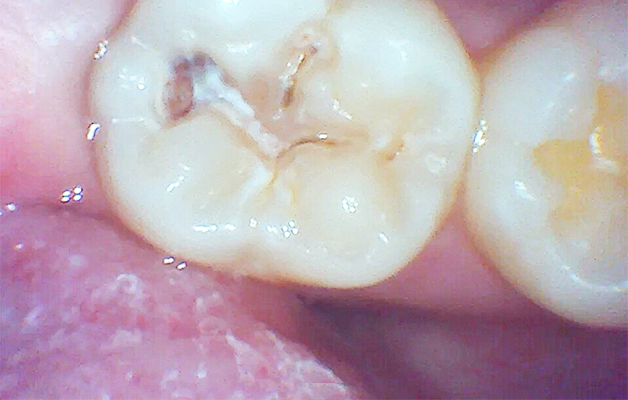

上記は、保険内治療でレジン充填治療(白い詰め物治療)を行った時の写真です。

治療時は口腔内カメラを活用し、治療前、治療中、治療後の状態を出来るだけ分かりやすくお伝えしています。